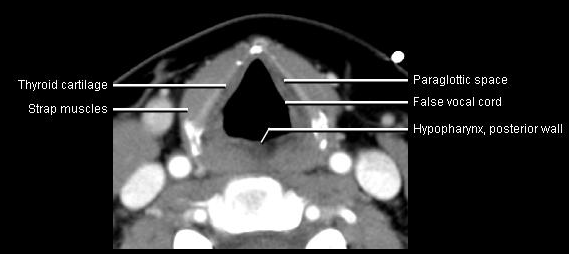

Phonation and dysphagia involve multiple coordinated structures in the larynx and pharynx. Radiation induced dysphagis appears to be related to dose to the phyaryngeal constrictor muscles and specific regions of the supraglottic and glottin larynyx.

Speech is impacted by doses to the epiglottis, base of tongue, aryepiglottic folds, false vocal cords upper esophageal sphincter and cricoid cartilage.

The mean laryngeal volume receiving > 50 Gy was a predictor of laryngeal edema. Vocal functions are usually well preserved with doses of 60 - 66 Gy. Dornfeld found a strong correlation between speech quality and dose to the ariepiglottic folds, pre-epiglottic space, false vocal cords and lateral pharyngeal walls at the level of the false vocal cords. A steep decrease in dose function was noted when doses exceeded 66 Gy.